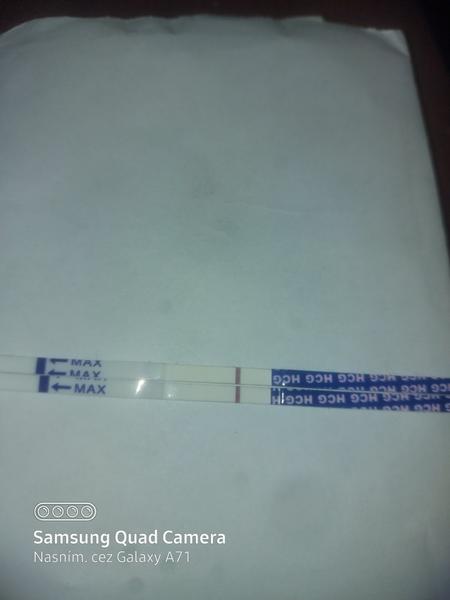

ahojte babule, mam taku otazku...mate skusenost ze pocas 3 dni vam nesilnela druha ciarka na teste ale bola rovnaka???ako duch????

Baby zaujíma ma či na tomto niečo vidíte,alebo nie,toto je v limite